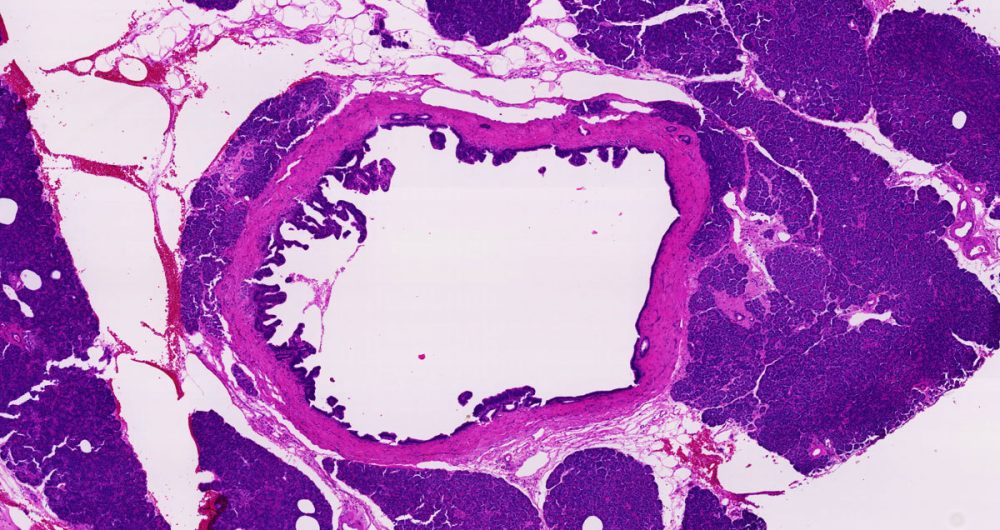

A fluid filled sac. Some tumors of the pancreas, including the serous cystadenomas and intraductal papillary mucinous neoplasms, form cysts. Cysts have a distinct appearance in CT scans. They are important to recognize because the treatment of cystic tumors can differ from that for solid tumors.

A term used to describe certain tumors which grow in finger-like projections. Pathologists use this term to describe some precancerous lesions in the pancreas (intraductal papillary mucinous neoplasm).

A term used to indicate that cancerous cells are present in the duct but have not yet invaded deeper tissues.